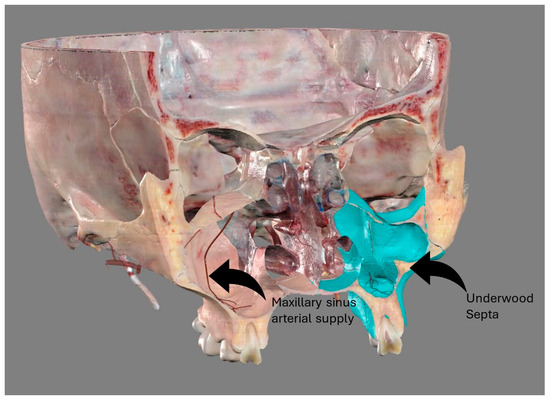

2.3. Evaluation of AAa

- The length of the arterial pathway in the mesiodistal dimension, on cross-section setting at 1 mm (Figure 2);

- The height of the maxillary bone crest in the cranio-caudal direction, on cross-section at the level of the first superior molar (Figure 3);

2.5. Evaluation of Underwood Septa

- The presence of the septa on cross-section (Figure 4);

- The height of the septa on cross-section setting from 2 mm to 0 mm, to better evaluate the maxillary sinus: this was measured from the apex of the septa to its bottom on the basal bone;

- The localization of the septa on cross-section;

- The orientation of the septa.